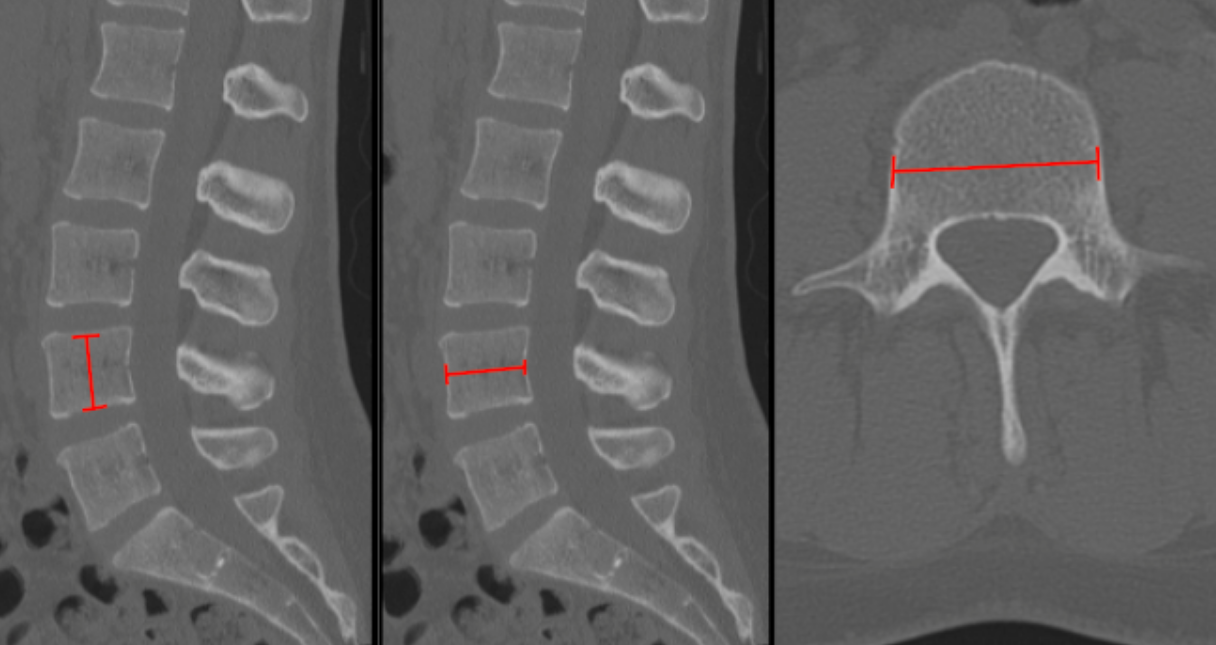

Anteroposterior (AP) Canal Diameter

Cross-Sectional Area of Canal (CSA)

Interpedicular Distance

CT Scan